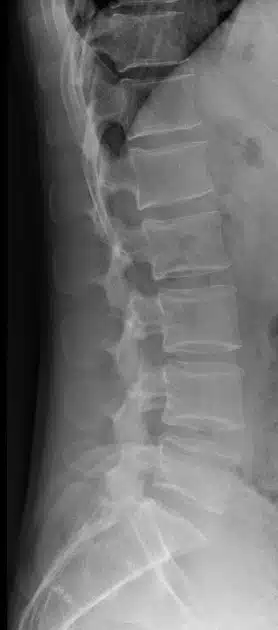

- X-ray – An X-ray uses the passage of electromagnetic waves to create shadow like images of bones and some organs. X-rays are quick and accessible but do a poor job evaluating soft tissues such as muscles and nerves. X-rays also expose the patient to a small amount of radiation.